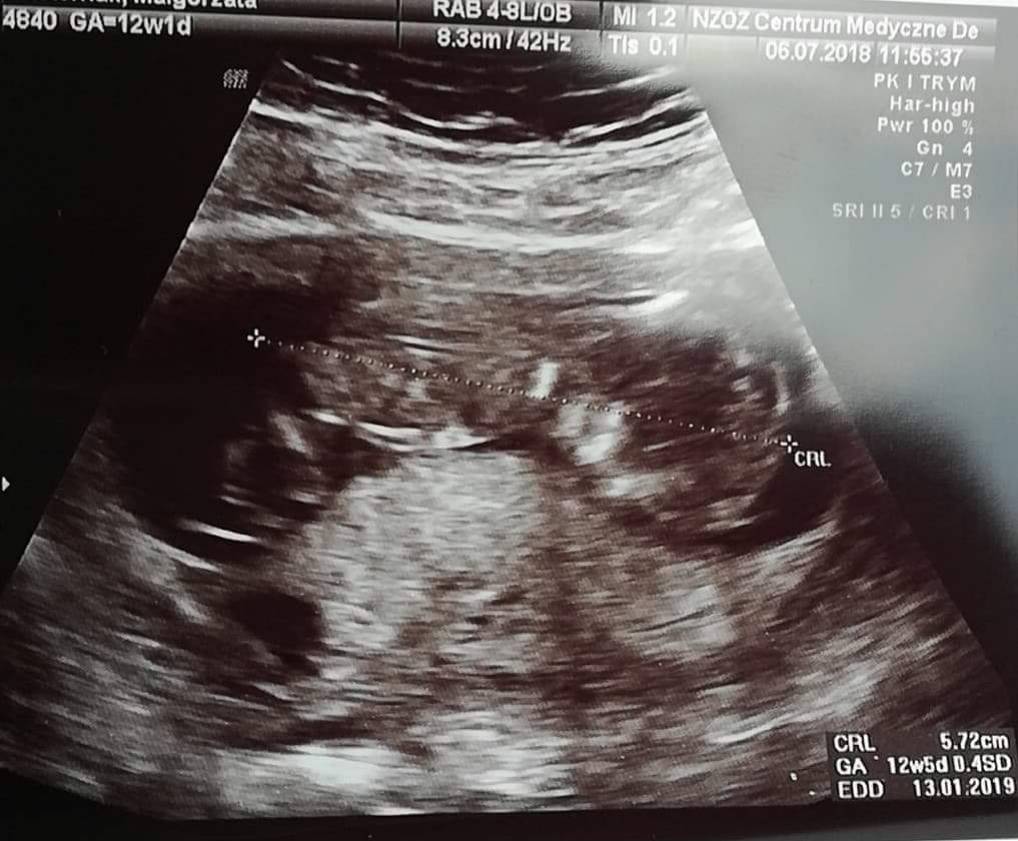

Jeeejciu [emoji173] Gratuluje, cos pieknego!Ja już po badaniu prenatalnym. Na USG wszystko wyszło ok, serduszko, żołądek, kość nosowa i karkówka, także nie ma powodu do zmartwień. Maleństwo ma już 5,7 cm niestety dupci nie chciało pokazać i o płci nie było szans porozmawiać [emoji7]Zobacz załącznik 874400

Piekne malenstwo [emoji7] super ze wszystko w porządku [emoji4]Ja już po badaniu prenatalnym. Na USG wszystko wyszło ok, serduszko, żołądek, kość nosowa i karkówka, także nie ma powodu do zmartwień. Maleństwo ma już 5,7 cm niestety dupci nie chciało pokazać i o płci nie było szans porozmawiać [emoji7]Zobacz załącznik 874400